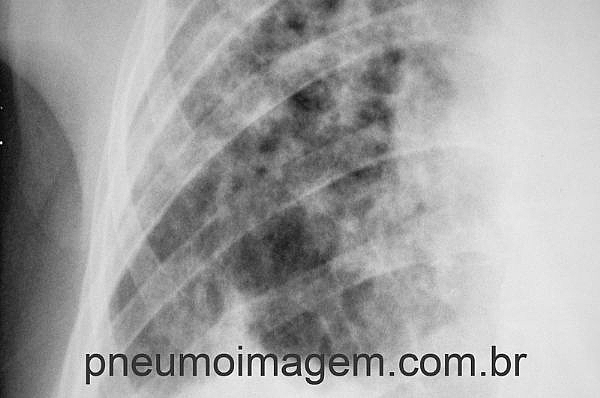

Hipertensão pulmonar (HP) é uma complicação grave da FPI e com impacto negativo no estado funcional e na qualidade de vida. Como os sintomas das duas condições se superpõem, é preciso manter um alto grau de suspeição para o correto diagnóstico. Investigação de HP deve ser realizada quando os sintomas forem desproporcionais à gravidade das lesões parenquimatosas causadas pela FPI.

Há pouca perspectiva de tratamento para HP em pacientes com FPI e isso se relaciona com pior prognóstico. Doentes que dessaturam abaixo de 89% no teste de caminhada de 6 minutos vivem menos em 4 anos (35%) em comparação àqueles que não dessaturam (68%). A pressão de artéria pulmonar verificada pelo ecocardiograma também se correlaciona com sobrevivência: valores menores que 50mmHg possuem maior tempo de vida (mais que 4 anos) em relação a valores maiores que 50mmHg, cujo tempo médio de vida é de pouco mais de seis meses.